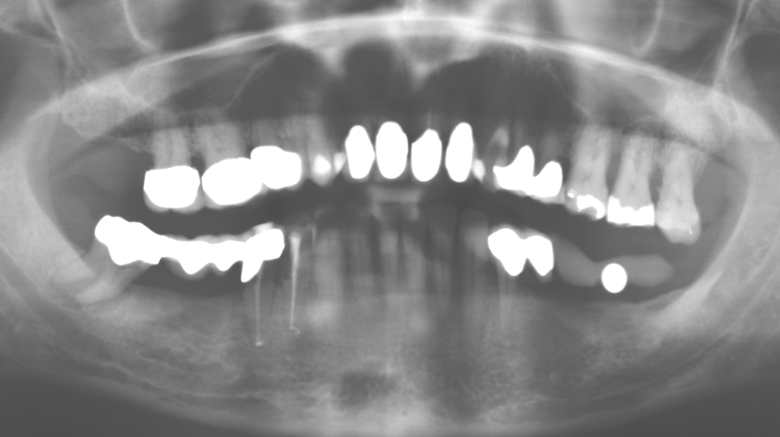

Il controllo decennale non ha rivelato alcuna indicazione dell'avanzamento della perdita di attaccamento clinico o della perdita di sostanza ossea perimplantare (Fig. 3).

Un'assistenza standardizzata e regolare a misura di rischio nell'ambito di SPT è la chiave per il successo del trattamento clinico a lungo termine nei pazienti con situazione periodontale compromessa. Ciò è particolarmente vero per i pazienti a cui vengono applicati impianti dopo il trattamento parodontale completato con successo (Fig. 11a e b).